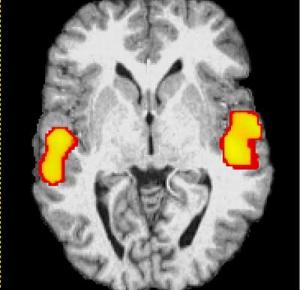

صورة للدماغ بواسطة جهاز المسح fMRI وقد تبين للعلماء أن الدماغ يبقى في حالة نشاط أثناء النوم، حيث يقوم بمعالجة المعلومات التي اختزنها طيلة النهار وترتيبها وتنسيقها في خلايا ...